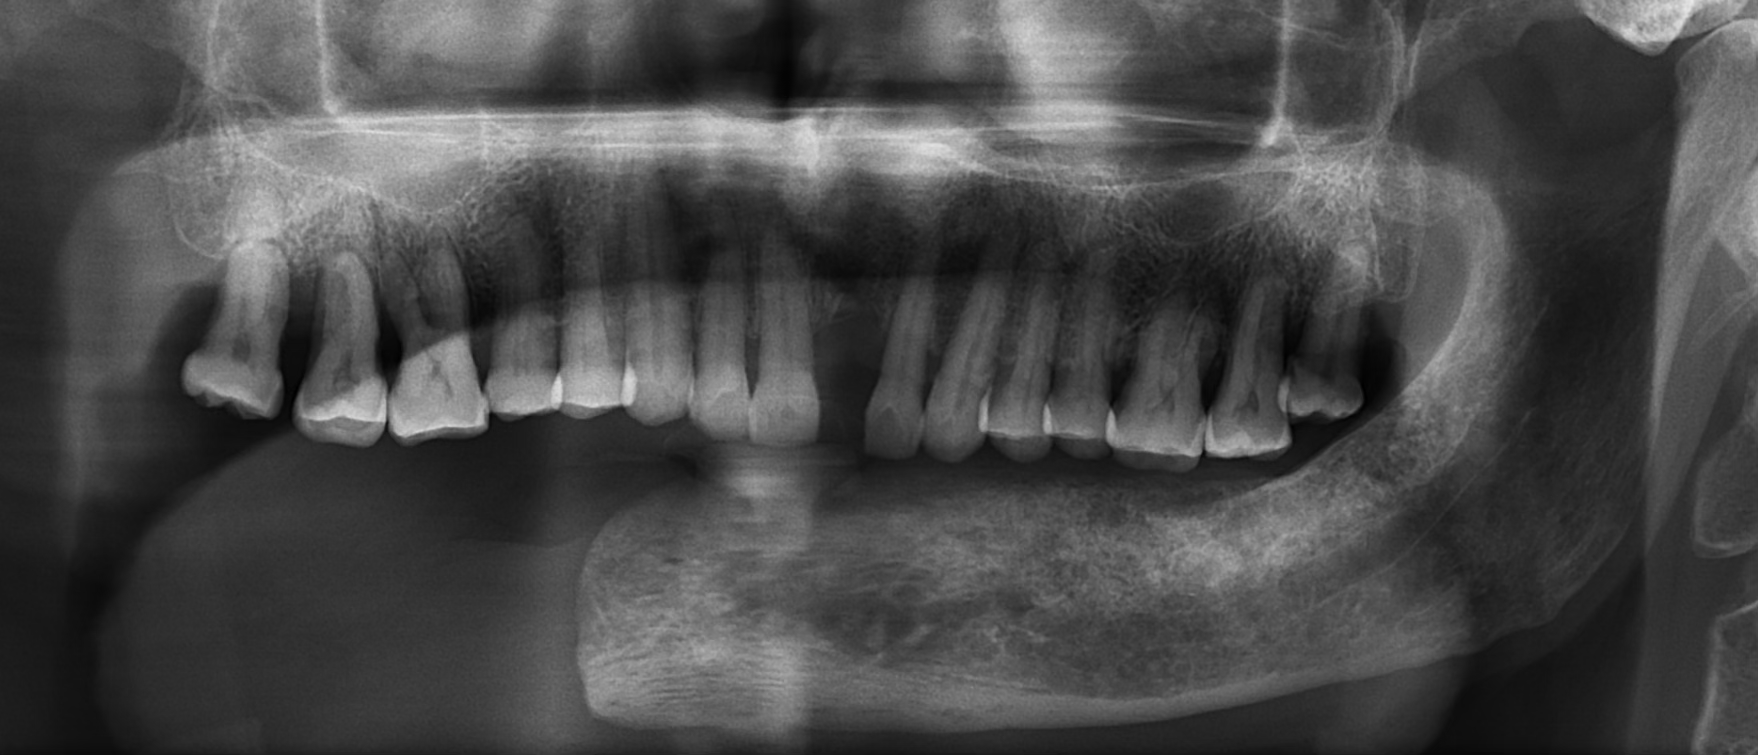

Comprehensive evaluation of oral cancer survivor post-hemimandibulectomy. Patient presented with missing teeth 16, 17, 25, 26, 31-37 and excised right mandible. Complete assessment of remaining bone and soft tissue.

A 72-year-old male oral cancer survivor visited our dental center after surgical removal of the right side of his mandible. Patient had multiple missing and attrited teeth with significant functional impairment. Treatment involved implant-supported lower teeth with PFM crowns and precision-attached removable denture for hemimandibulectomy rehabilitation.